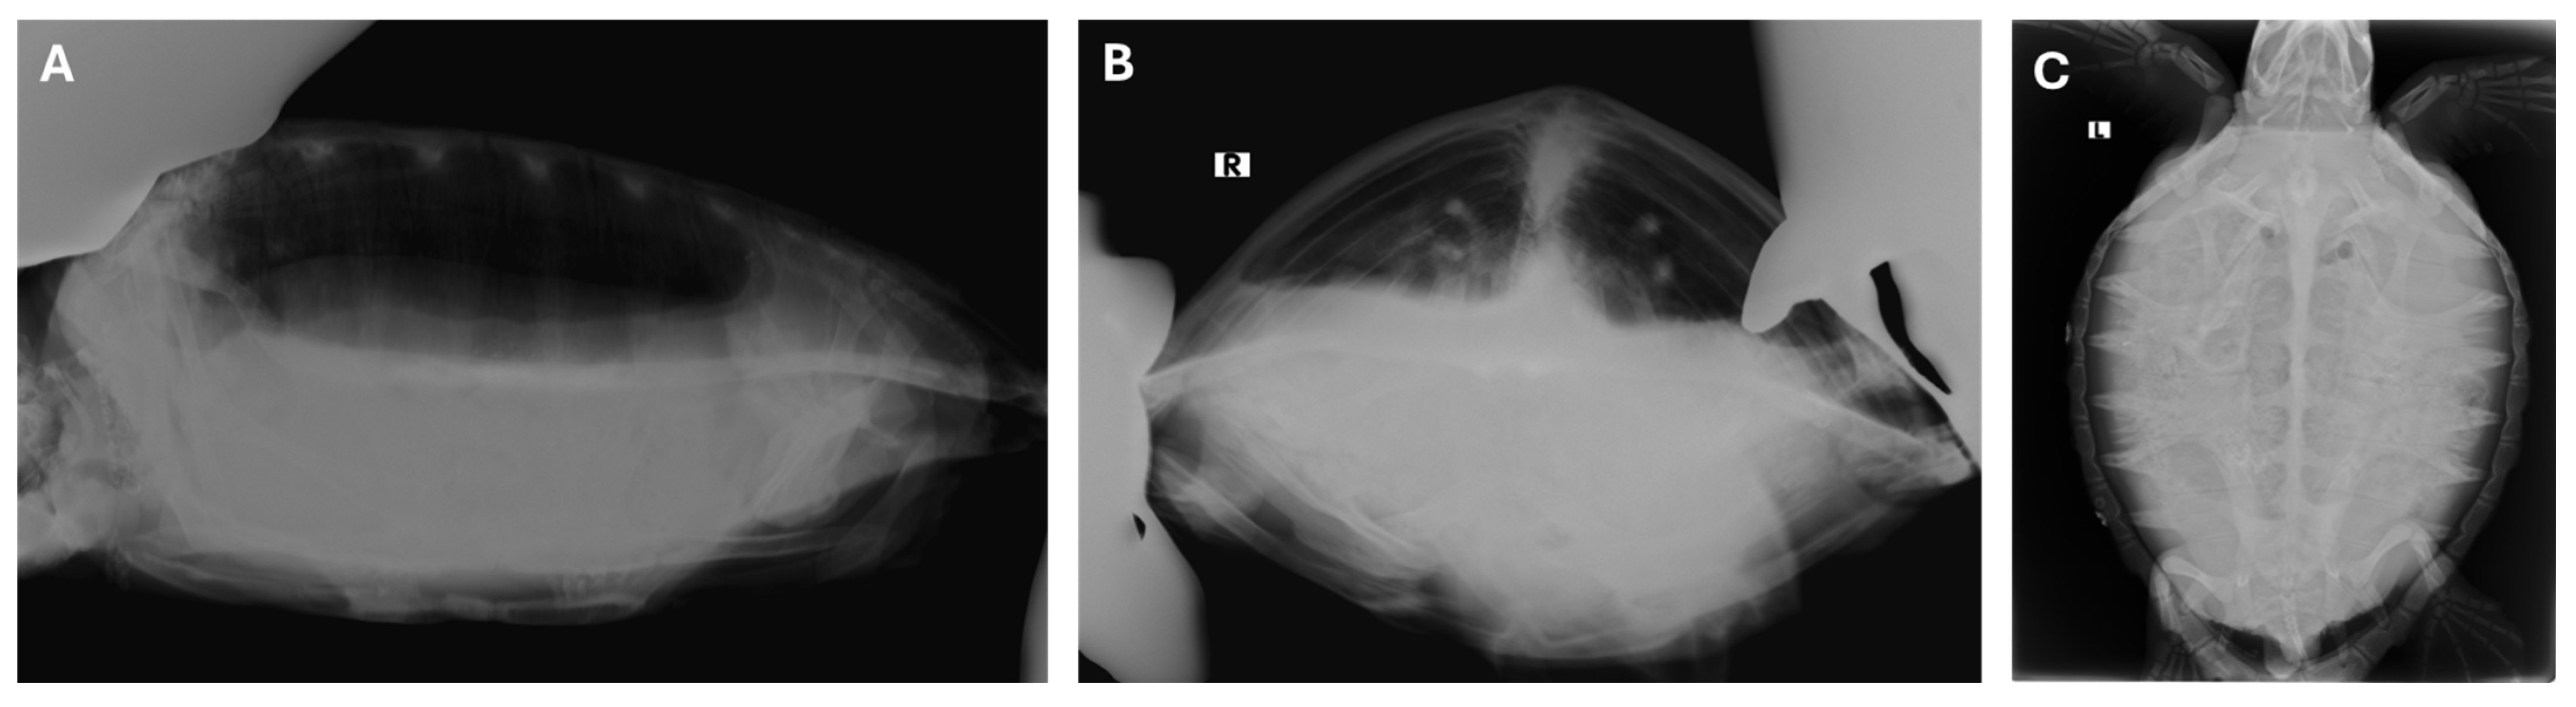

2.2. Diagnostic Tests